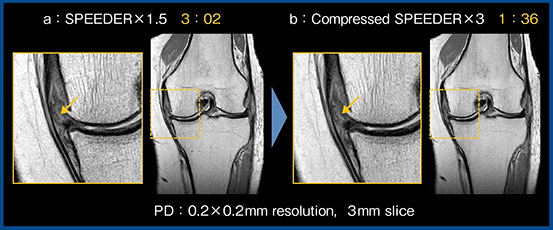

一般的に,高分解能撮像では撮像時間が延長するため,高速化技術は非常に重要である。Compressed SPEEDERはCSとparallel imaging(PI)を組み合わせた高速化技術である。PIで用いられるMulti sensitivity Mapは,コイル1チャンネルあたり2セット以上の感度マップを作成することで画像展開の精度を向上させている。これをCSの逐次計算にも用いることで,画像展開の精度がさらに向上し,より明瞭な画像が得られる。また,Compressed SPEEDERはエンコード方向を長軸方向に設定しても,従来のPI(SPEEDER)で問題となる折り返しアーチファクトが生じないため,整形領域の撮像には非常に相性が良い。図3はPD強調画像であるが,SPEEDER 1.5倍速(3分02秒)の画像(a)で認められた内側半月板の逸脱と水平断裂(↓)が,Compressed SPEEDER3倍速(1分36秒)の画像(b)でも画質が劣化することなく同様に確認できる。

図3 PD強調画像におけるSPEEDER(a)とCompressed SPEEDER(b)の比較

(内側半月板の逸脱・水平断裂)